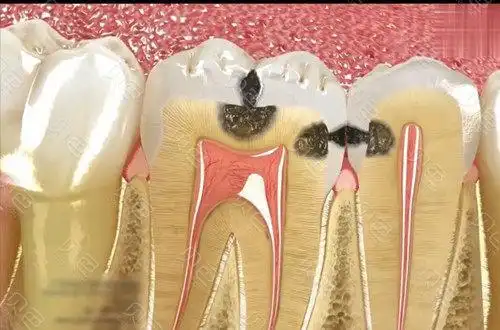

一例邻面龋,修补后复发,看看我的修补过程

牙齿邻面龋齿

邻面龋和龋齿